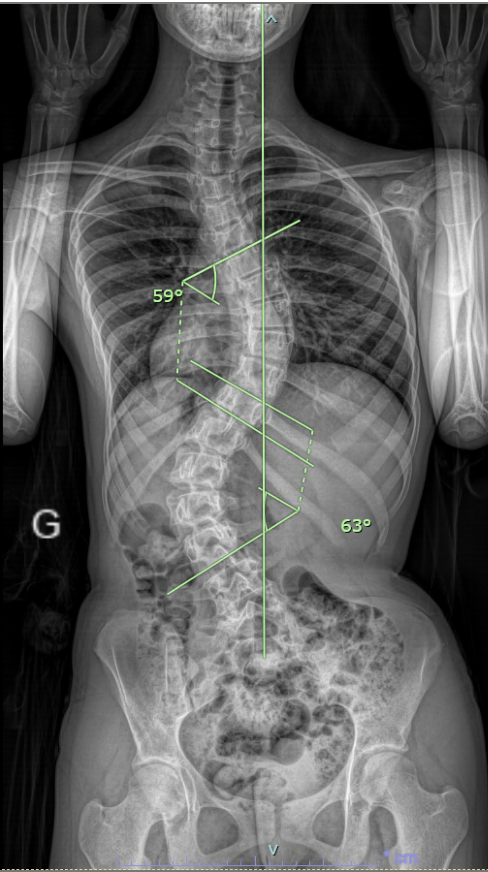

Scoliose de l'enfant et l'adolescent

Je suis spécialisé dans la prise en charge complète des scolioses de l’enfant et de l’adolescent, qu’elles soient idiopathiques (AIS), congénitales (hémivertèbre, malformations vertébrales complexes) ou neuromusculaires.

Mon expertise couvre l’ensemble du spectre thérapeutique, de la modulation de croissance chez l’enfant en croissance à l’arthrodèse vertébrale et aux corpectomies dans les déformations sévères ou évolutives, y compris la chirurgie après traitement conservateur par corset.